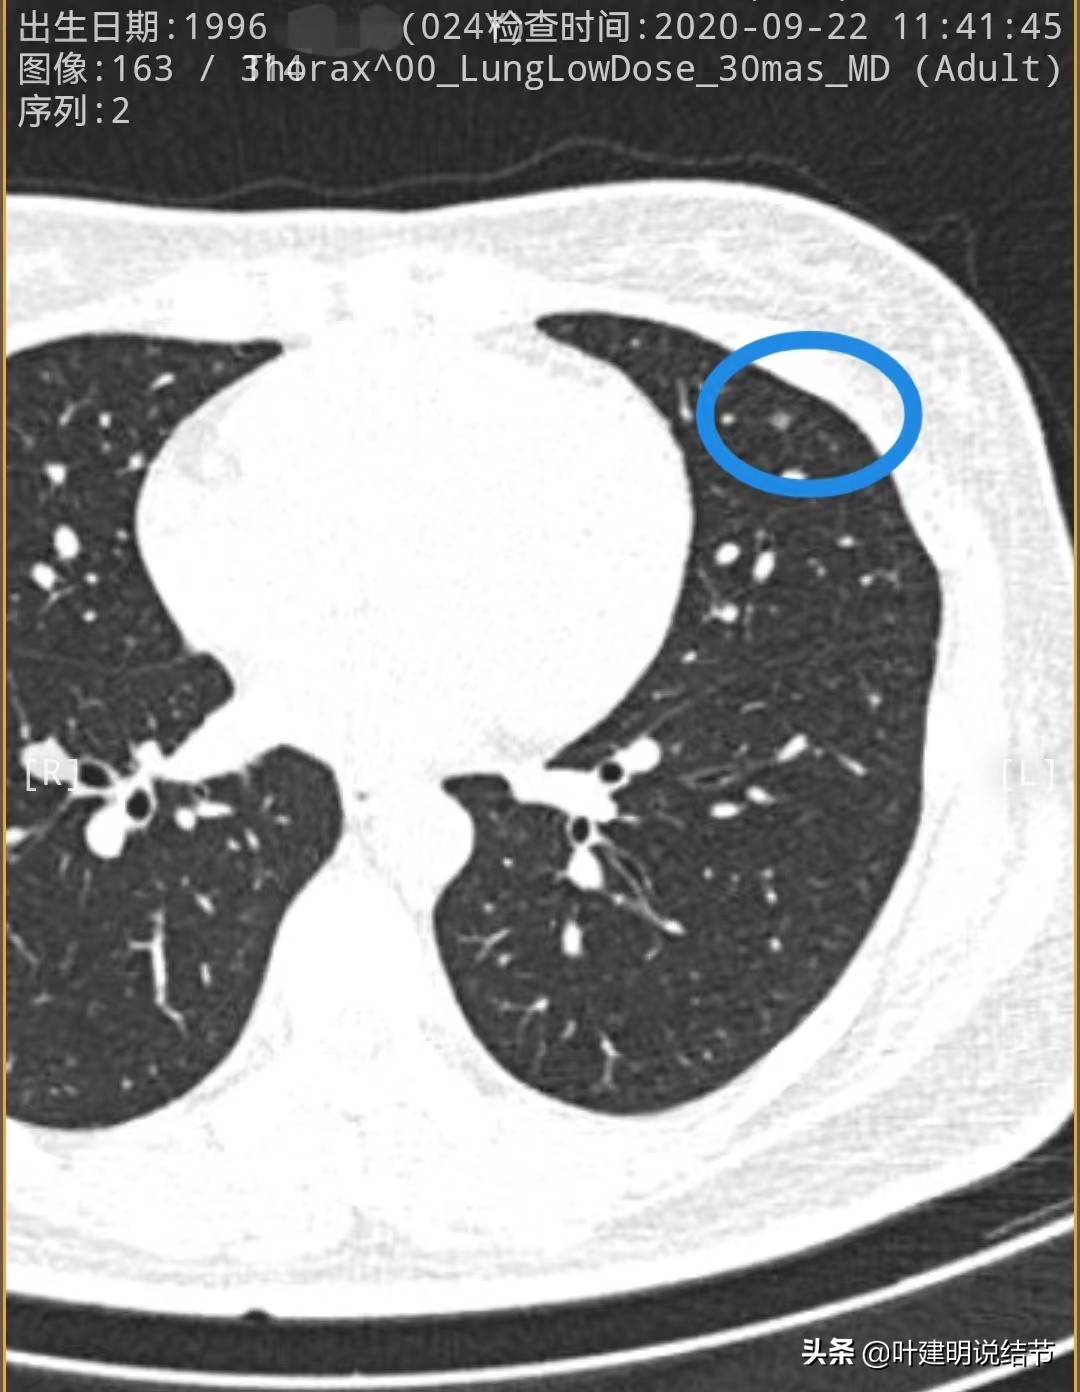

先来看2020年时的CT图像:

左上叶舌段密度偏高结节,边界较清,原位癌可能,也可以是良性结节,边缘膨胀性略差